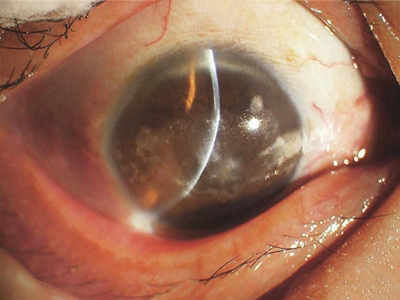

带状角膜病变眼球有白色条带图

带状角膜病变初期表现为钙质性灰白色或白色混浊斑,混浊斑可逐渐扩大并相互融合成较大的白色斑块,患者可出现畏光、流泪及眼痛等刺激症状。